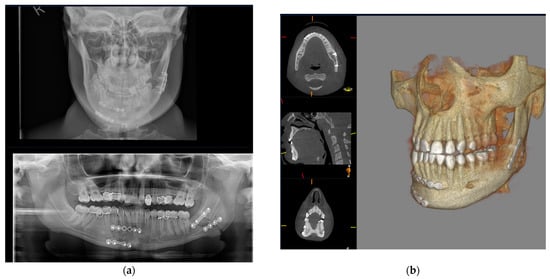

3.1. Cone Beam CT for Assessment of Dentoalveolar Fractures

3.2. Cone Beam CT for Assessment of Mandibular Fractures